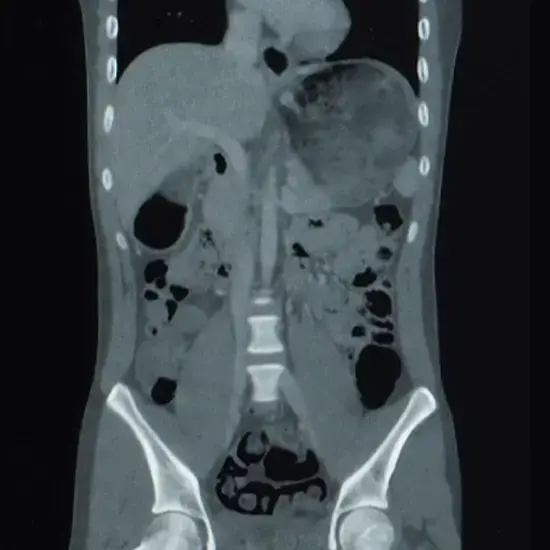

CECT Lower Abdomen - Test, Cost & Procedure

CECT Lower Abdomen

A contrast-enhanced computed tomography of the lower abdomen is a diagnostic imaging technique used to visualise and assess the organs and structures in the abdominal region.

CECT of the lower abdomen is commonly performed to diagnose a range of medical conditions affecting organs such as intestines, kidneys, bladder, reproductive organs and pelvic structures, suspected cancers and evaluate the treatment progress.

A diagnostic imaging technique called CECT lower  Abdomen is used to produce finely detailed images of the blood vessels, soft tissues, bones, and internal organs. Intravenous contrast dye is injected into the body during this test to help provide a clear picture of the blood vessels.